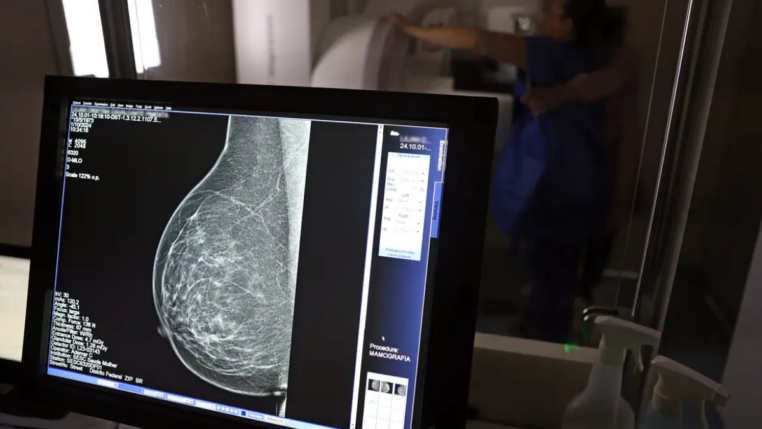

No mês de conscientização sobre o câncer de mama, um relatório destaca a importância de acesso igualitário ao rastreamento e tratamento da doença. Segundo o Atlas da Radiologia no Brasil, do Colégio Brasileiro de Radiologia e Diagnóstico por Imagem (CBR), o acesso aos mamógrafos ainda é um desafio.

O país tem 6.826 equipamentos registrados, sendo 96% em funcionamento. Metade deles está disponível no Sistema Único de Saúde (SUS), responsável por atender 75% da população. Isso equivale a 2,13 mamógrafos por 100 mil habitantes dependentes do SUS.

Na saúde suplementar, que cobre 25% da população, o cenário é mais favorável: 6,54 aparelhos por 100 mil beneficiárias, quase o triplo da rede pública. O Acre exemplifica essa disparidade — são 35,38 mamógrafos por 100 mil habitantes na rede privada, contra 0,84 no SUS.

Há disparidades regionais. Roraima tem a menor proporção (1,53 por 100 mil), seguida do Ceará (2,23) e Pará (2,25). A Paraíba lidera o ranking (4,32), à frente do Distrito Federal (4,26) e do Rio de Janeiro (3,93).

Segundo a coordenadora da Comissão Nacional de Mamografia do CBR, Ivie Braga de Paula, todos os estados têm número suficiente de aparelhos para o exame. Mas um conjunto de gargalos dificultam o acesso e geram subutilização.

“Há problemas de informação, de comunicação, de acesso e logística, principalmente na Região Norte. Por exemplo, os mamógrafos ficam nas cidades mais centrais e a população ribeirinha não consegue chegar. Às vezes, tem que andar seis a sete horas de barco para fazer uma mamografia. Até nos grandes centros, as pacientes da periferia não têm informação suficiente e enfrentamdificuldades para marcar e chegar em um local com mamógrafo”, diz Ivie.

O Brasil tem uma cobertura muito baixa de mamografias: 24%. O ideal recomendado pela Organização Mundial da Saúde é de 70%. Mesmo em lugares como o estado de São Paulo, que tem a maior concentração de mamógrafos do país, a taxa gira em torno de 26%.

Em setembro, o Ministério da Saúde ampliou as diretrizes de rastreamento, recomendando que mulheres entre 40 e 49 anos realizem mamografias, mesmo sem sintomas. De acordo com o Instituto Nacional do Câncer (Imca), mais de 73 mil mulheres recebem o diagnóstico de câncer de mama anualmente no Brasil.

“O que é efetivo na redução da mortalidade é você descobrir o tumor antes de ter sintoma clínico. Quanto menor o tumor, melhor para a gente descobrir o tratamento e maior a chance de cura. E a gente só consegue fazer isso com exames de imagem”, diz Ivie.

Ela explica que no caso de diagnóstico de um câncer de mama com menos de 1 cm, a chance de cura é de 95% em cinco anos, independentemente se ele é do tipo mais agressivo. “E esses tumores só vão ser detectados na mamografia. Essas pessoas que têm que ir fazer mamografia são mulheres saudáveis. Não são mulheres doentes”, acrescenta.